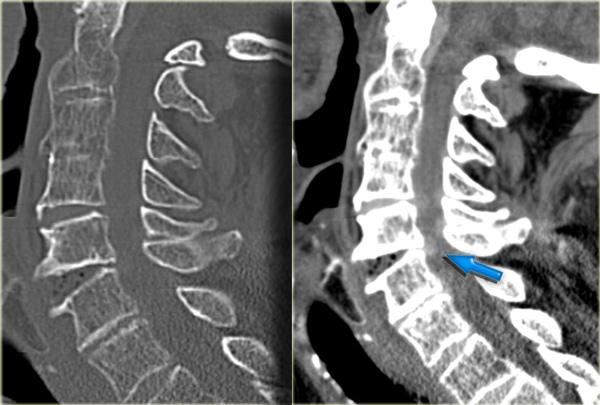

Bên trái là hình ảnh của một phụ nữ 44 tuổi bị ngã trên băng.

Sau đó bà bị ngã lần thứ hai vào sáng hôm sau, và sau đó mất hoàn toàn vận động và cảm giác.

Khám thực thể cho thấy liệt hai chi dưới kèm yếu nhẹ chi trên bên phải.

Ban đầu được đề xuất chẩn đoán tổn thương tủy trung tâm.

X-quang bình thường.

Các dấu hiệu bao gồm:

- Các mảnh xương nhỏ tách ra từ mặt khớp trên và dưới

- Khoang gian gai rộng ra tại C5-6

- Sưng nề mô mềm ở mức này về phía sau

- Hẹp nhẹ khoang đĩa đệm tại mức C5-6.

Các dấu hiệu CT này rất tinh tế và dường như không tương xứng với vấn đề thần kinh.

Trong trường hợp như vậy, MRI là bước tiếp theo cần thực hiện.